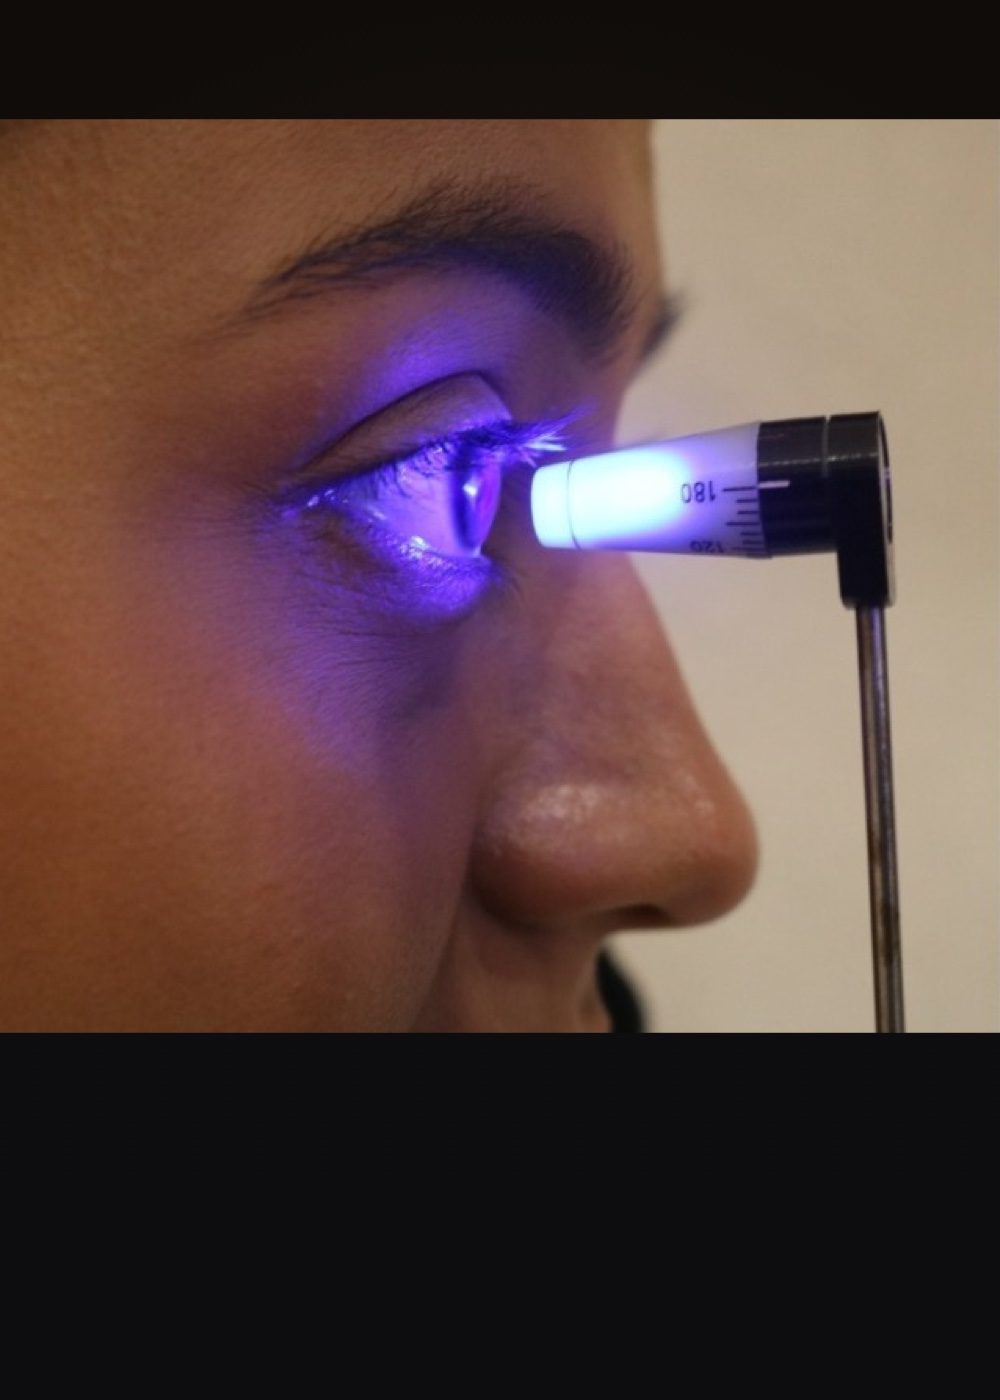

Topografia Corneal

La topografía corneal es un examen que se utiliza para crear un mapa detallado de la superficie corneal.